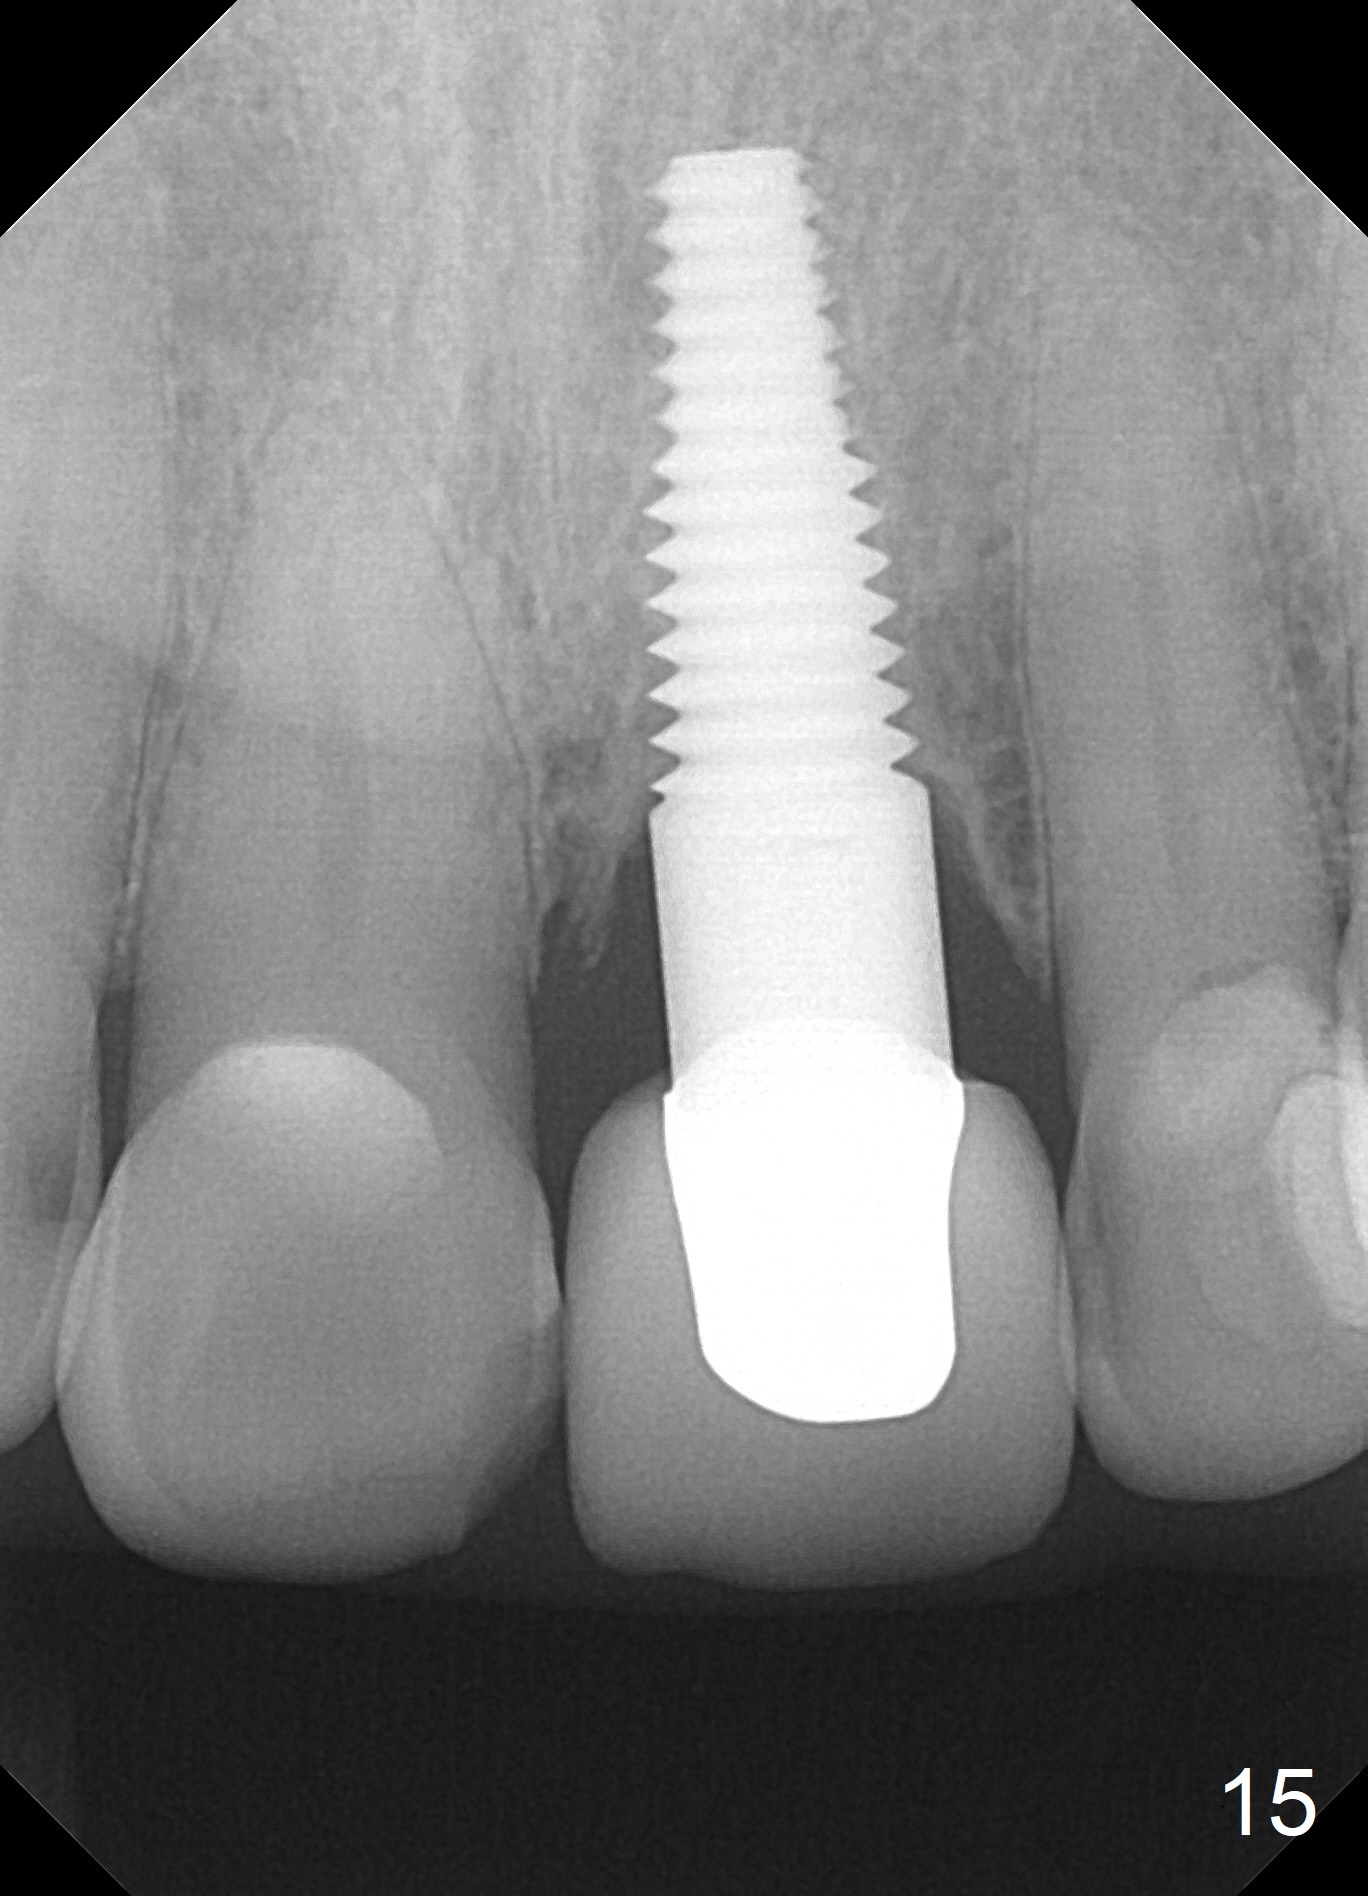

Postop tenderness lasts for two days. The palatal swelling is unnoticeable 7 days postop (Fig.9 *, as compared to A in Fig.8). The bone remains stable around the implant (Fig.10), while the gingiva healthy around the immediate provisional (Fig.11) 5 months postop. Due to insurance limit, the permanent restoration is delayed (16 months postop, Fig.12). The patient is satisfied with the function and appearance 3 years 8 months postop (21 months post cementation, Fig.13,14). PA is taken 4 years 1 month postop (2.5 years post cementation, Fig.15). The lamina dura forms from the most coronal threads (Fig.16). Although there is no bone loss around the implant (Fig.17), metal starts to show 5 years 2 months postop (Fig.18 ^), probably related to the buccal placement, too large the implant for the site or buccal plate atrophy (Fig.19).